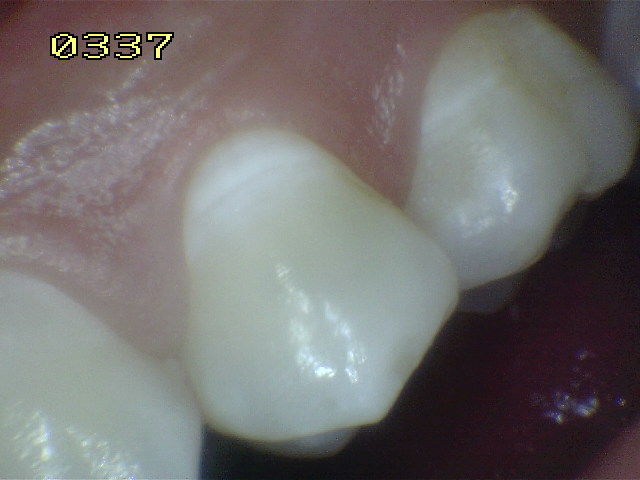

Casos clínicos de fluorosis leve.

Esmalte liso, traslúcido y cristalino acompañado con gruesas líneas horizontales blanquecinas.

Las manchas opacas por fluorosis leve deben diferenciarse con los códigos1 y 2 de ICDAS. En las fluorosis el esmalte aparece brillante; mientras que en el proceso de caries se observa un blanco aspecto de tiza. (sin brillo)